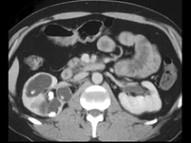

问题 女,45岁,右腰部疼痛伴血尿,请根据所示图像,选择最可能诊断 ( )

选项 A、右肾积水 B、右肾结石合并右肾盏扩张积水 C、右肾出血 D、右肾结石 E、右肾结核

答案 B